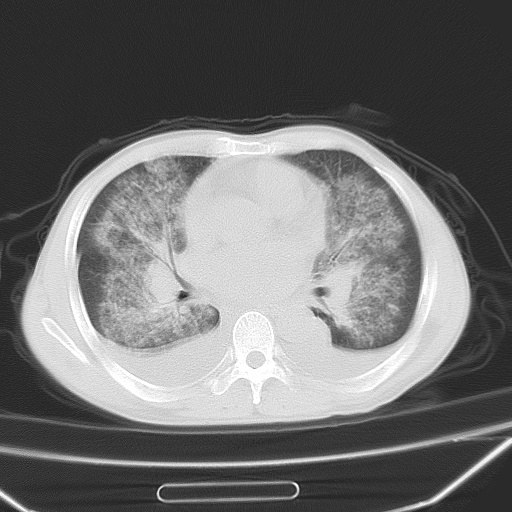

男、42岁、咯血3天。既往有甲亢、贫血、血尿蛋白尿史多年。血象:wbc:6.   中性粒:70.6%。

双肺野对称性磨玻璃影,分布于内中带,双侧胸水,患者有咯血。

双肺野广泛对称性磨玻璃影、实变影,以肺门为中心,主要分布于内中带,符合典型肺泡性肺水肿;伴双侧胸腔少量游离积液。结合患者既往病史且咯血就诊,支持多因素(尿毒症等)所致之肺水肿、肺出血、胸水;影像表现暂不考虑心源性水肿,且症状也不太符。需密切随诊结合临床治疗等进一步明确。

心影增大密度略低,双肺磨玻璃样高密度影及双侧胸腔积液,考虑心功能不全继发双肺肺水肿及双侧胸腔积液。心影密度略低,考虑贫血所致。